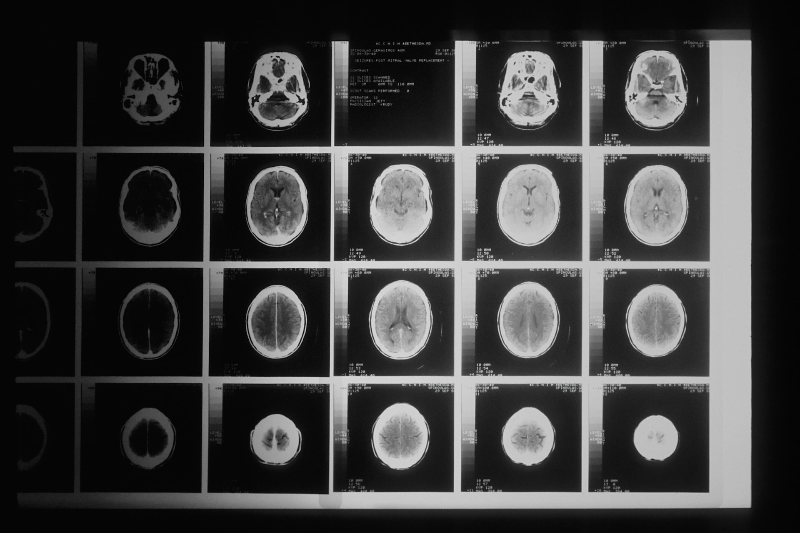

우선 연구 결과를 살펴보면, 정치적 신념을 지키거나 바꾸려고 할때 뇌의 어떤 부분이 활성화되는지를 살펴본 결과, 참가자의 대부분은 비정치적인 문장에 대해 자신의 의견을 바꾸는 경우가 많았지만, 정치적 신념을 바꾸지 않는 사람들의 뇌에서는 <편도체>와 <뇌섬엽>이 활성화가 되는 사실을 관찰할 수 있었습니다.

편도체는 감정을 조정하는 기관으로 공포 및 불안에 대한 학습 및 기억에 대한 역할을 한다고 알려져 있습니다. 편도가 제거되는 경우에는 공포나 불안에 대한 반응을 유발하지 상황을 학습하지 못한다고 합니다.

뇌섬엽은 내부적, 외부적으로 일어나는 상황에서 뇌가 체계적인 이해와 관여를 하면서 자신 자신을 인식하고 사회적 상호작업을 가능하게 한다고 알려져 있습니다. 뇌섬엽은 자신에 대한 공정한 대우에 모니터링을 하기도 하고 배고픔, 통증 등 주관적인 감각을 느끼게 돕기도 한다고 합니다.

조나스 캐플런 교수의 연구에서 이러한 <편도체>와 <뇌섬엽>이라는 부분이 활성화는 감정적인 처리나 공격적인 반응에 나타나는 뇌의 활성화 현상이라는 측면에서 정치적으로 반대되는 사실을 마주하면, 이성적인 부분보다는 감정적인 영역이 활성화된 인과관계를 연구를 통해 발견할 수 있었다고 합니다.